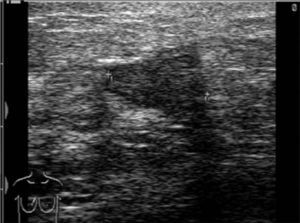

In all 3 patients, ultrasound studies revealed poorly defined hypoechoic lesions (Fig. 1) with no axillary involvement. Mammography demonstrated a nodule in the left lower quadrant of the right breast in only one patient, while in the other 2 the test was negative. Magnetic resonance imaging (MRI) showed alterations consistent with malignancy and breast abscesses in the second and third patients, while in the first patient the test was negative.

Fig. 1.

Poorly-defined hypoechoic lesion.